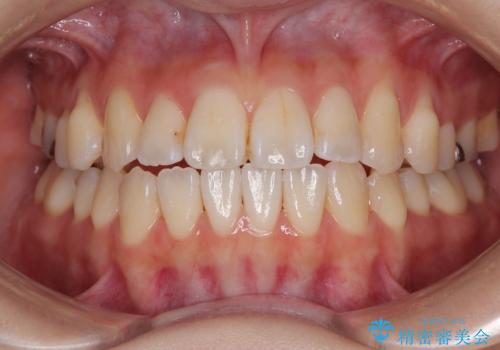

舌の突出癖が原因 インビザライン矯正による開咬改善

- 前歯の開咬を気にして来院された患者様です。

開咬の治療は、前歯を閉じるように動かすとともに、上下臼歯を圧下(骨内にめり込ませる)させることで進めて行きます。

インビザラインは臼歯の圧下を効果的に行えるため、インビザラインを用いて矯正治療を行うこととしました。

オープンバイトは舌の突出癖により誘発され、治療後も突出癖が残っている容易に後戻りしてしまいます。

治療期間を短縮するためにも、舌突出癖の改善が極めて重要となります。

特にインビザラインではIPRという歯と歯の間を削る処置を多用するため、後戻りによりスペースが生じやすくなるため、治療初期段階での舌のトレーニングが必須となります。